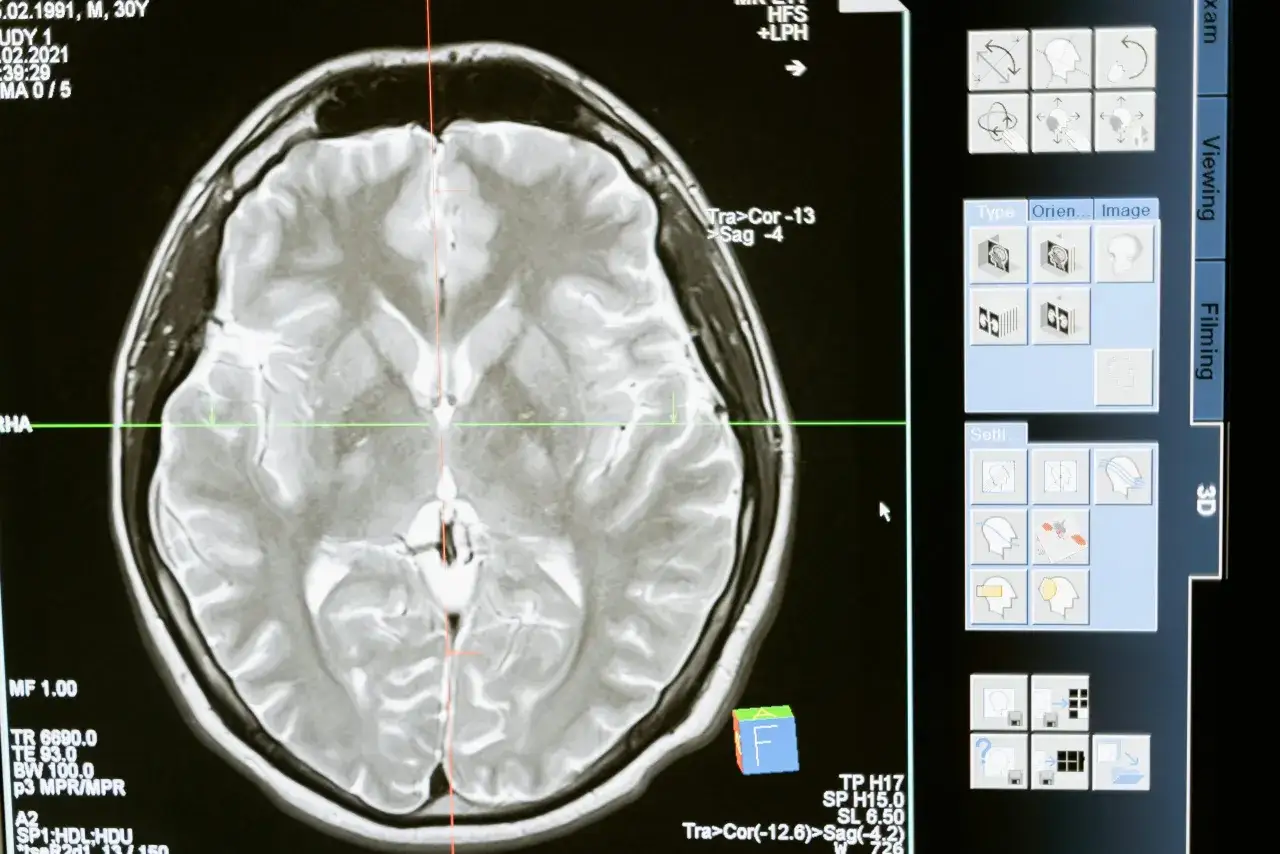

Istnieją dwa główne typy udarów: niedokrwienny i krwotoczny. Udar niedokrwienny, stanowiący około 85% wszystkich przypadków, powstaje w wyniku zablokowania naczynia krwionośnego w mózgu. Udar krwotoczny, rzadszy, ale często poważniejszy, wynika z pęknięcia naczynia i wylewu krwi do tkanki mózgowej.

Choć ogólne objawy udaru są podobne dla obu typów, istnieją pewne subtelne różnice. Udar niedokrwienny często rozwija się stopniowo, podczas gdy krwotoczny może mieć bardziej nagły początek, często z towarzyszącym silnym bólem głowy. Niezależnie od typu, kluczowe jest szybkie rozpoznanie udaru i wezwanie pomocy.